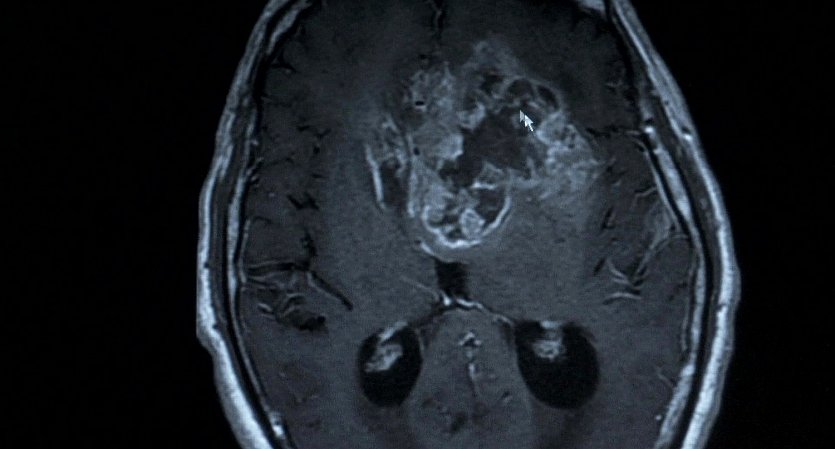

Name: Stopped.on.Track.2011_00088

Source: Blu-ray 1080p